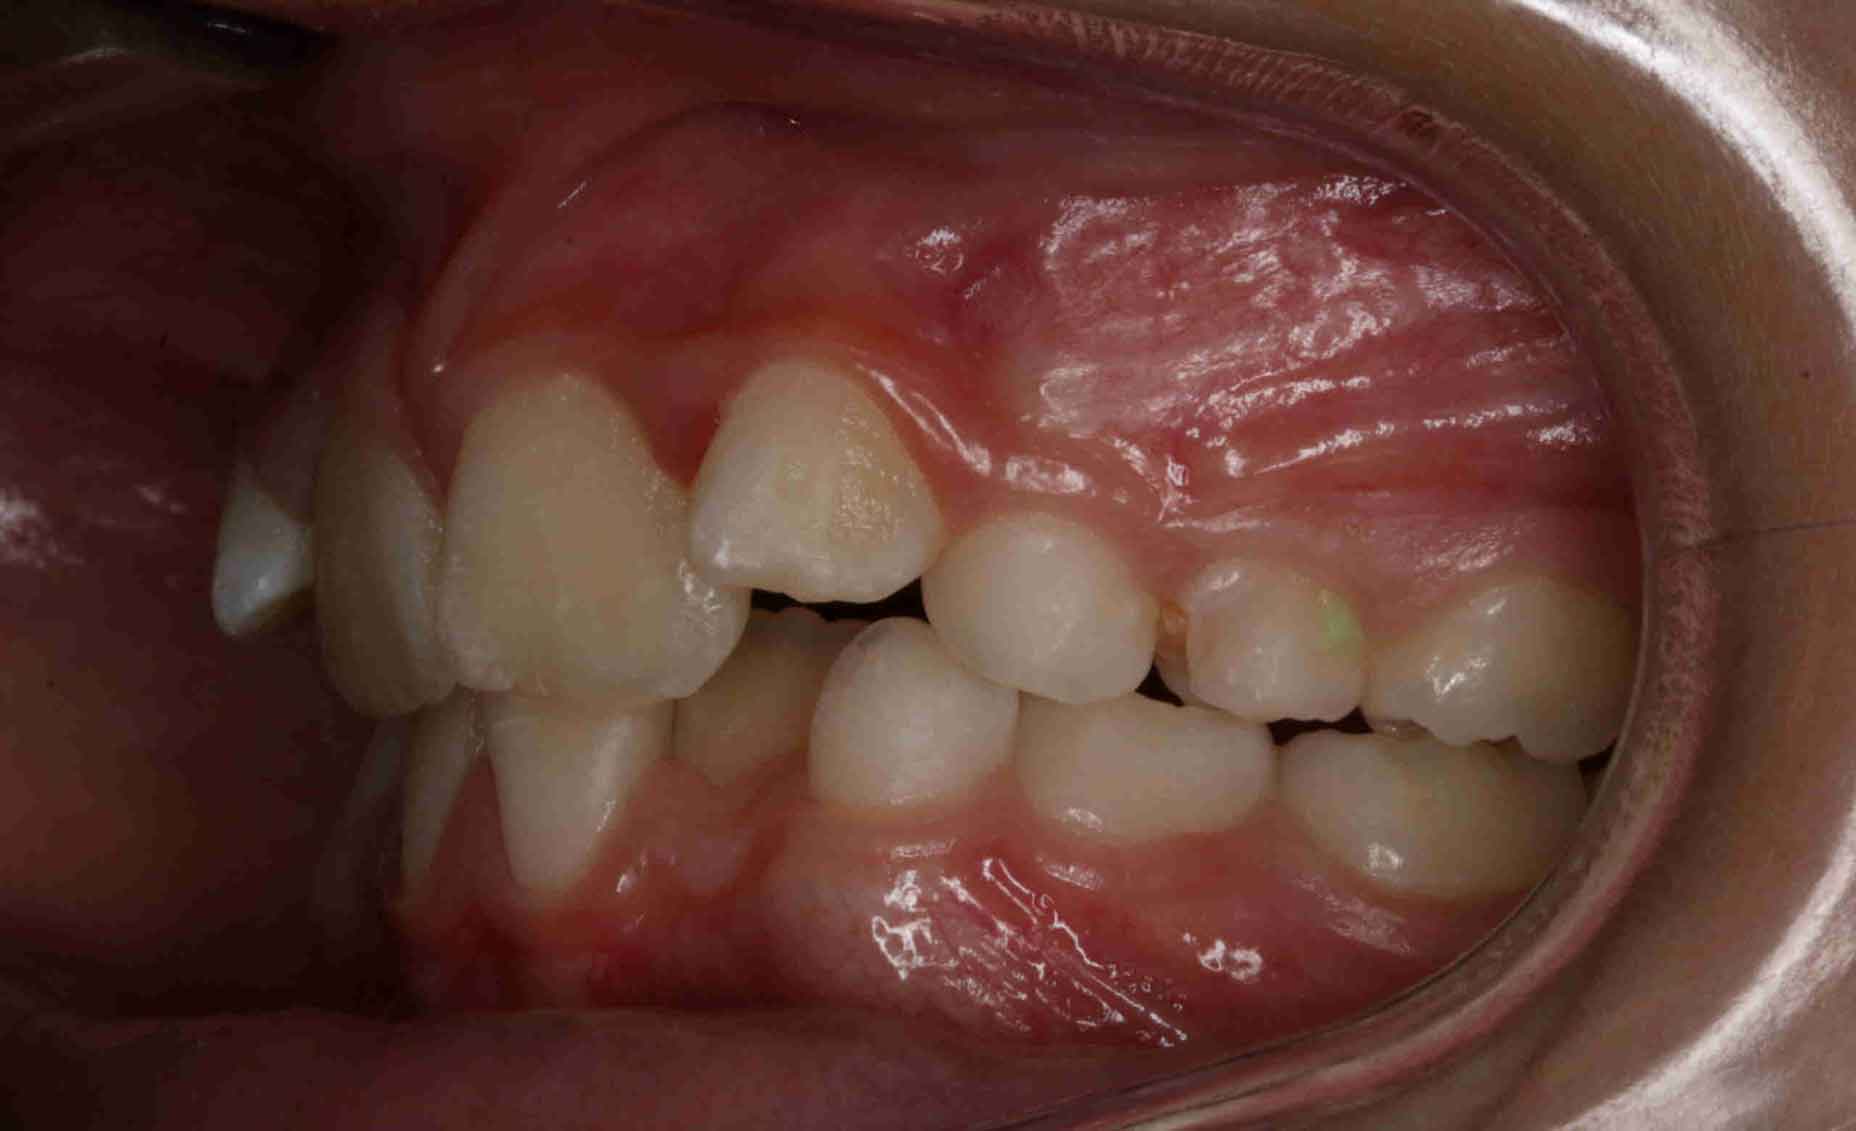

Caninos Impactados

En las siguientes imágenes puedes ver distintos resultados del tratamiento, deslizando la barra central de un lado a otro.